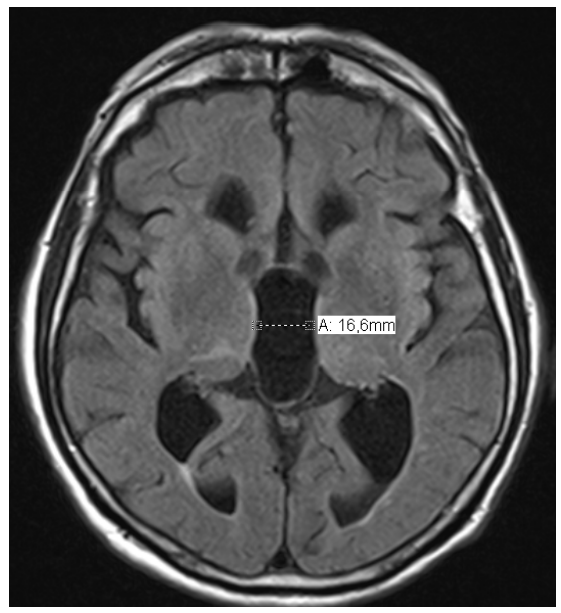

Evans Index >0.3 (x/y)

Dilatation of the third ventricle